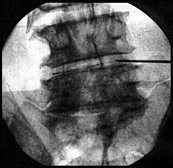

Je nach Erfolg der Injektionstherapie bei Blockade der Wirbelgelenke, schließt sich eine Thermosonden am Wirbelgelenk an. Hierbei steht die Behandlung der Abnutzungen eines Wirbelgelenks im Vordergrund. Unter Röntgen oder CT-Kontrolle führt man eine Thermosonde direkt an das schmerzende Wirbelgelenk. Durch eine gepulste Radiofrequenzsonde erhitzt sich die Spitze der Sonde. Auf diese Weise wird ein kleiner Bereich verödet und die Leitung der Schmerzfasern unterbrochen. Diese Verfahren kann sowohl an der Lendenwirbelsäule, wie auch an der Halswirbelsäule durchgeführt werden.

Diese Behandlung kann erforderlicherweise mehrmals und von verschiedenen Wirbelgelenken durchgeführt werden.